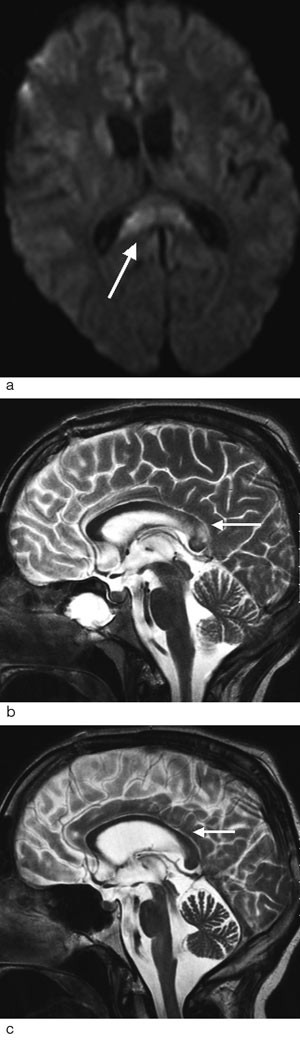

Diffus aksonal skade er ikke nødvendigvis diffus i sin utbredelse. Tvert imot forekommer disse lesjonene med et ganske typisk distribusjonsmønster. De fleste lesjoner er små (5 – 15 mm) og lokalisert til hvit substans og overgangen mellom grå og hvit substans i frontallappene og temporallappene (fig 2a). Ved kraftigere traumer kan det i tillegg påvises lesjoner i corpus callosum og i hjernestammen (fig 2b og c). Avhengig av hvilke strukturer som er omfattet av skaden, kan diffus aksonal skade graderes i grad 1 – 3 (tab 2) (25).

| Eventuelt i øvre cerebellare pedunkler |

Lesjonene er vanligvis multiple, ofte så mange som 15 – 20, og kan deles i hemoragiske og ikke-hemoragiske (25, 27). De ikke-hemoragiske lesjonene som forekommer hyppigst, representerer ødem i hjernevevet, mens de hemoragiske skadene trolig skyldes lekkasje av blod fra små kar som forløper langs aksonene og som rives over ved traumet. Blødningene er typisk punktformede, og de minste betegnes gjerne mikroblødninger (fig 2d).

MR-teknikker ved diffus aksonal skade

Hurtige T2-vektede spinnekkosekvenser og FLAIR-sekvenser er MR-teknikker som er følsomme for å påvise endringer i hjernens vanninnhold, og økt vanninnhold vises som områder med høyt signal. Ved FLAIR-sekvensen blir signalet fra det frie vannet i cerebrospinalvæsken undertrykket, og dette øker sensitiviteten for å oppdage ødem i hjernevevet ved diffus aksonal skade (fig 2a og c) (28).

Gradientekko T2*-vektede bilder (såkalt hemosekvens) er velegnet for å påvise blodnedbrytingsprodukter, og lesjoner med blodprodukter fremtrer som signaltomme områder (fig 2d) (25). Størrelsen på disse områdene er betydelig større enn selve blodansamlingen. Dette skyldes at de paramagnetiske blodproduktene forstyrrer magnetfeltet i et større område. Mens lesjonene forårsaket av ødem kan forsvinne etter dager eller uker, vil lesjonene som er forårsaket av mikroblødninger kunne bestå i måneder til år da nedbrytingsproduktene innleires i hjernevevet (14, 25).

Nye MR-teknikker

Diffusjon. Diffusjonsvektet MR er en relativt ny teknikk som viser termisk bevegelse av vannmolekyler i vevet. Ved diffus aksonal skade inntrer endringer i vanndiffusjonen da aksonskade med kollaps av cellestrukturen kan gi endring av vannmolekylenes bevegelighet (29). Områder i hjernevevet med redusert diffusjon tyder på en irreversibel celleskade som vil føre til vevsnekrose (fig 3). Studier har vist at diffusjonsvektet MR er en mer følsom teknikk enn de tradisjonelle MR-sekvensene (27, 30). Siden blant annet mikroblødninger vil være lettere å påvise med andre MR-sekvenser, må diffusjonssekvenser likevel benyttes som et tillegg til, og ikke som erstatning for, de konvensjonelle teknikkene.